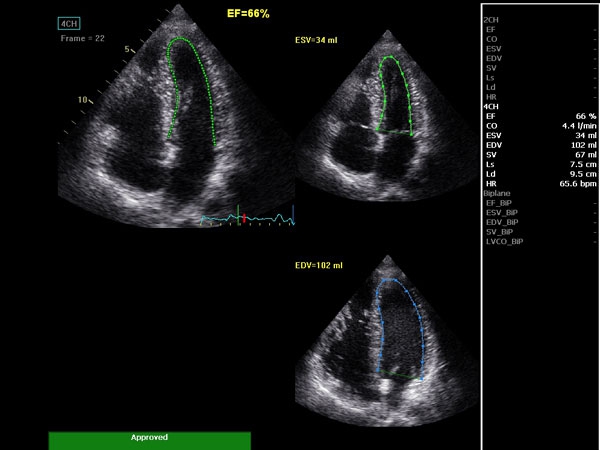

• AutoEF (Auto Ejection Fraction) — функция автоматической недоплеровской количественной оценки глобальной сократительной функции левого желудочка с выделением зоны интереса по технологии спекл-трекинга.

AUTO 2D EF:

Да

• 2D Auto EF